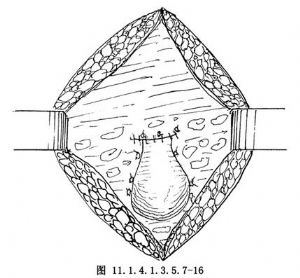

11.7 7.關閉腹腔

以4號絲線連續縫合子宮頸前後腹膜關閉腹膜。將各附件殘端置於腹膜外(圖11.1.4.1.3.5.7-16)。